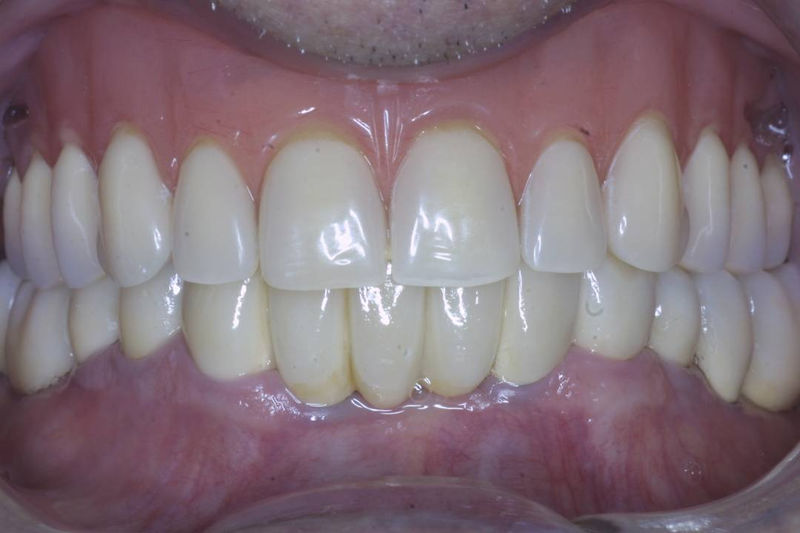

Amplia gama de tratamientos para mejorar la apariencia de la sonrisa, corrigiendo el color, la forma, el tamaño, la alineación y la posición de los dientes. Los procedimientos más comunes y solicitados incluyen el blanqueamiento dental, las carillas y coronas, así como las resinas.

Son restauraciones que cubren toda la cara frontal del diente, generalmente empleadas en el sector anterior y cuya finalidad es primariamente estética.

Restauraciones fabricadas en el laboratorio con materiales estéticos, los cuales cubren de manera total dientes anteriores y posteriores. Se utilizan primariamente para restaurar dientes con caries, fracturas y/o defectos amplios, así como soportes de puentes. Para poder enviar el caso al laboratorio se toman impresiones utilizando materiales de impresión o técnicas modernas digitales.